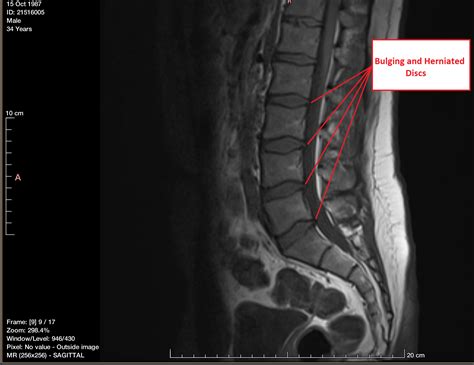

Back pain is one of the most common reasons people seek medical attention, and frequently, the culprit lies within the spinal discs—the rubbery cushions located between the individual vertebrae that act as shock absorbers. When you experience back or neck pain, you may hear terms like "bulging disc" and "herniated disc" used almost interchangeably. However, understanding the herniated disc versus bulging distinction is crucial, as they describe different anatomical conditions that can require different approaches to treatment and recovery. While both involve issues with the spinal discs, the mechanics of how they affect the spine and the surrounding nerves differ significantly.

A bulging disc is often considered a degenerative process, similar to the natural aging of the spine. In this scenario, the outer, tougher layer of the disc weakens, causing the disc to extend or "bulge" outside its normal perimeter between the vertebrae.

• It typically involves a larger portion of the disc's circumference—usually more than 25% of the disc.

• It is frequently a gradual process that happens over many years.

• Many people have bulging discs without even realizing it, as they may not cause immediate pain or nerve compression.

Defining a Herniated Disc

A herniated disc (also known as a ruptured or slipped disc) is a more acute condition. In this case, the tough outer layer of the disc actually tears or cracks, allowing the jelly-like nucleus pulposus to leak out entirely.

• The protrusion is usually much more localized, affecting a smaller area than a bulging disc.

• Because the internal material leaks out, it is more likely to come into contact with nearby spinal nerves.

• This contact can cause significant pain, inflammation, numbness, or weakness in the areas served by those nerves.